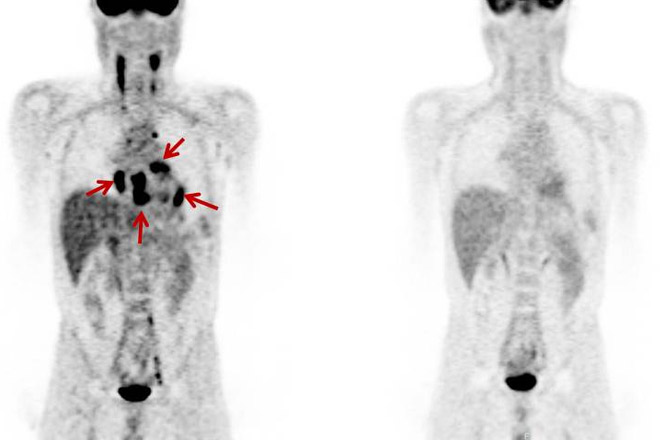

不整脈を来たした心サルコイドーシス

心筋に集積を認め、活動性のある心サルコイドーシスと診断された(左下図)。治療後は心筋への異常集積は消失し、治療効果が確認された(右下図)。